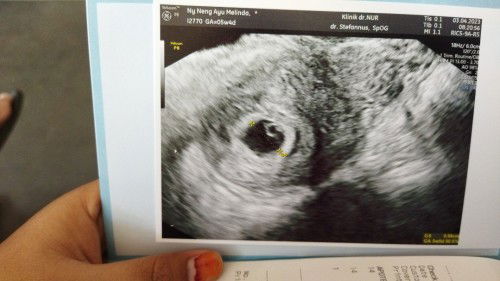

bersyukur alhamdulillah

Alhamdulillah periksa pertama sudah 5 minggu 5 hari, alhamdulillah Ya Alloh penantian 2 tahun meski pun masih kecil belum terlalu terlihat tapi saya bersyukur banget. Terimakasih ya Alloh dan mom mom yang sudah mendoakan dan ngasih semangat, #bantusharing